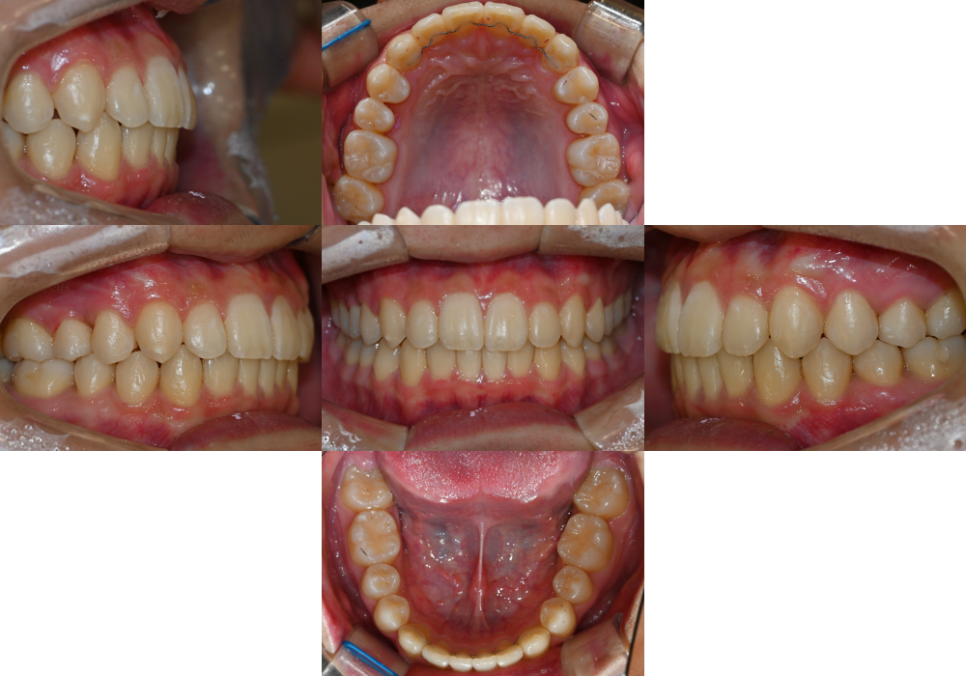

23.04.26

구강 내 모습을 보면

위아래 전치부 치열이

삐뚤빼뚤한 덧니가 나타났습니다.

특히 아래쪽의 총생이

더 심하게 나타나 있었는데요.

더불어, 오른쪽 위 작은 어금니 하나가

정상적인 치열보다 안쪽으로

이소맹출된 것을 관찰할 수 있었습니다.

그로 인해 오른쪽 위아래

작은 어금니 부위에

반대 교합이 나타나 있었습니다.

추가로, 위 아랫니의 관계를 살펴보았을 때

윗니가 아랫니를 과하게 덮고 있는

과개 교합으로 판독할 수 있었습니다.